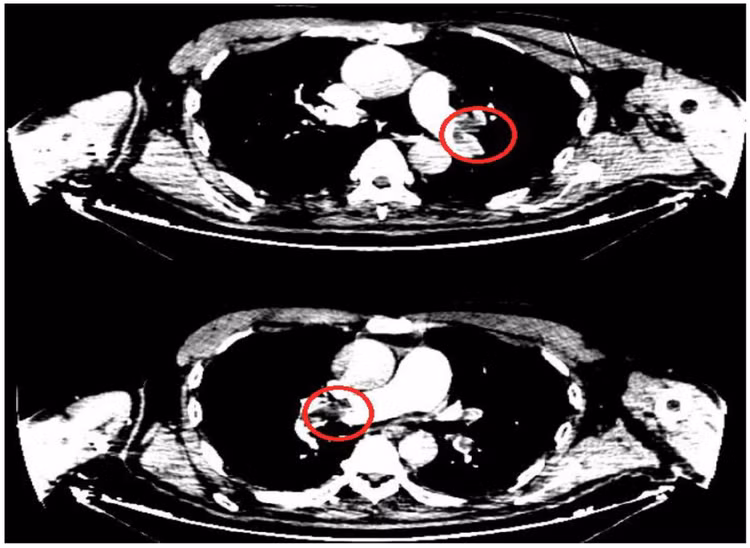

Nghi ngờ tình trạng thuyên tắc phổi cấp, bệnh nhân được chụp cắt lớp vi tính chẩn đoán huyết khối động mạch phổi hai bên và lập tức chuyển Bệnh viện Đa khoa tỉnh Quảng Ninh.

![]() |

| Hình ảnh huyết khối động mạch phổi cả 2 bên của bệnh nhân. - Ảnh BVCC |

Hai trường hợp chúng tôi điều trị vừa qua xảy ra rất đột ngột, nặng nề với tình trạng huyết khối mạch phổi một hoặc hai bên trên nền bệnh nhân có yếu tố nguy cơ. Các trường hợp này đều được nơi điều trị ban đầu phát hiện sớm, chính xác và chuyển khoa Hồi sức tích cực điều trị tiêu sợi huyết kịp thời, vì vậy người bệnh hồi phục tốt, di chứng tối thiểu.